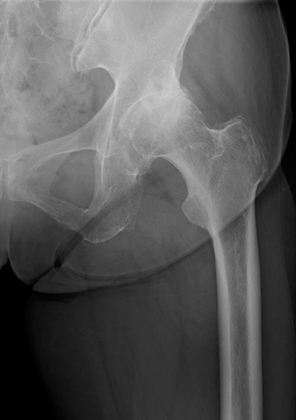

![]() 術前レントゲン |

①変形性股関節症

何らかの原因で関節軟骨が摩耗して変性し、股関節が変形する疾患です。主な症状は、股関節の痛み、股関節の動きの制限、ひきずり足歩行(跛行)です。変形が進行すると、変形した側の脚(あし)の長さが短くなり、左右の脚の長さが違ってくることもあります。加齢や関節の使い過ぎなどによって起こる「一次性変形性股関節症」と、生まれつき寛骨臼のかぶりが浅いこと(臼蓋形成不全)が原因で起こる「二次性変形性股関節症」があります。欧米では一次性が大半を占めますが、日本では二次性が多いという特徴があります。寛骨臼のかぶりが浅いと、大腿骨頭を十分に覆うことができないため、関節軟骨の狭い範囲に負担が集中し、変形が進行しやすくなります。